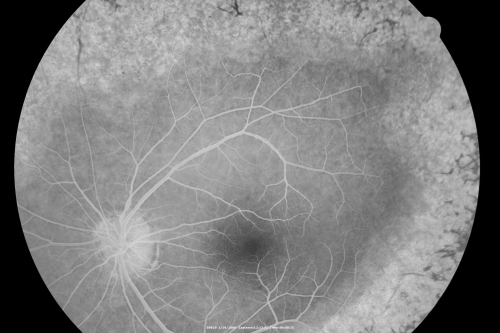

Acute Zonal Occult Outer Retinopathy

45-year-old man  noticed a few years ago peripheral vision blurriness in the left eye and also some central vision loss.   Previous to that, as far as he knows, the two eyes were okay.

VISUAL ACUITY:  OD:  20/20;  OS:  20/40.